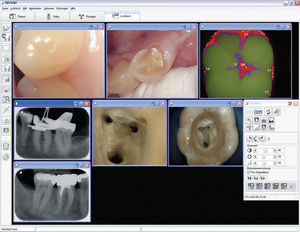

Desde la toma y edición de imágenes de rayos X y de la cámara, el intercambio de imágenes en la nube hasta la planificación de implantes y plantillas de taladrado: con VistaSoft confluyen todos los hilos del sistema de imágenes dentales. El principio ...